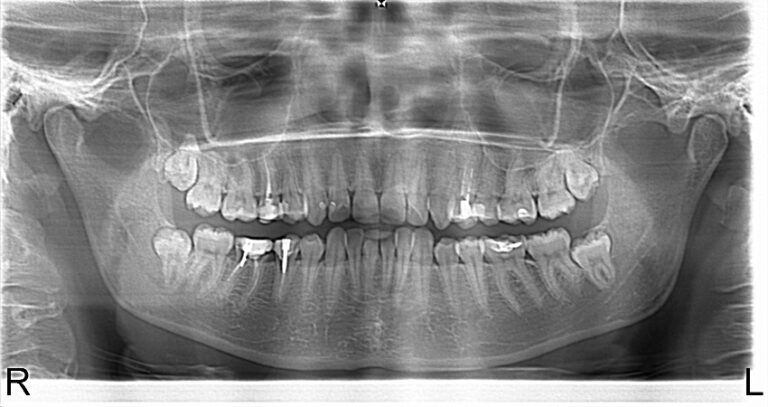

Photo 1.Panoramic roentgenogram of a 46-year-old patient A. before treatment.